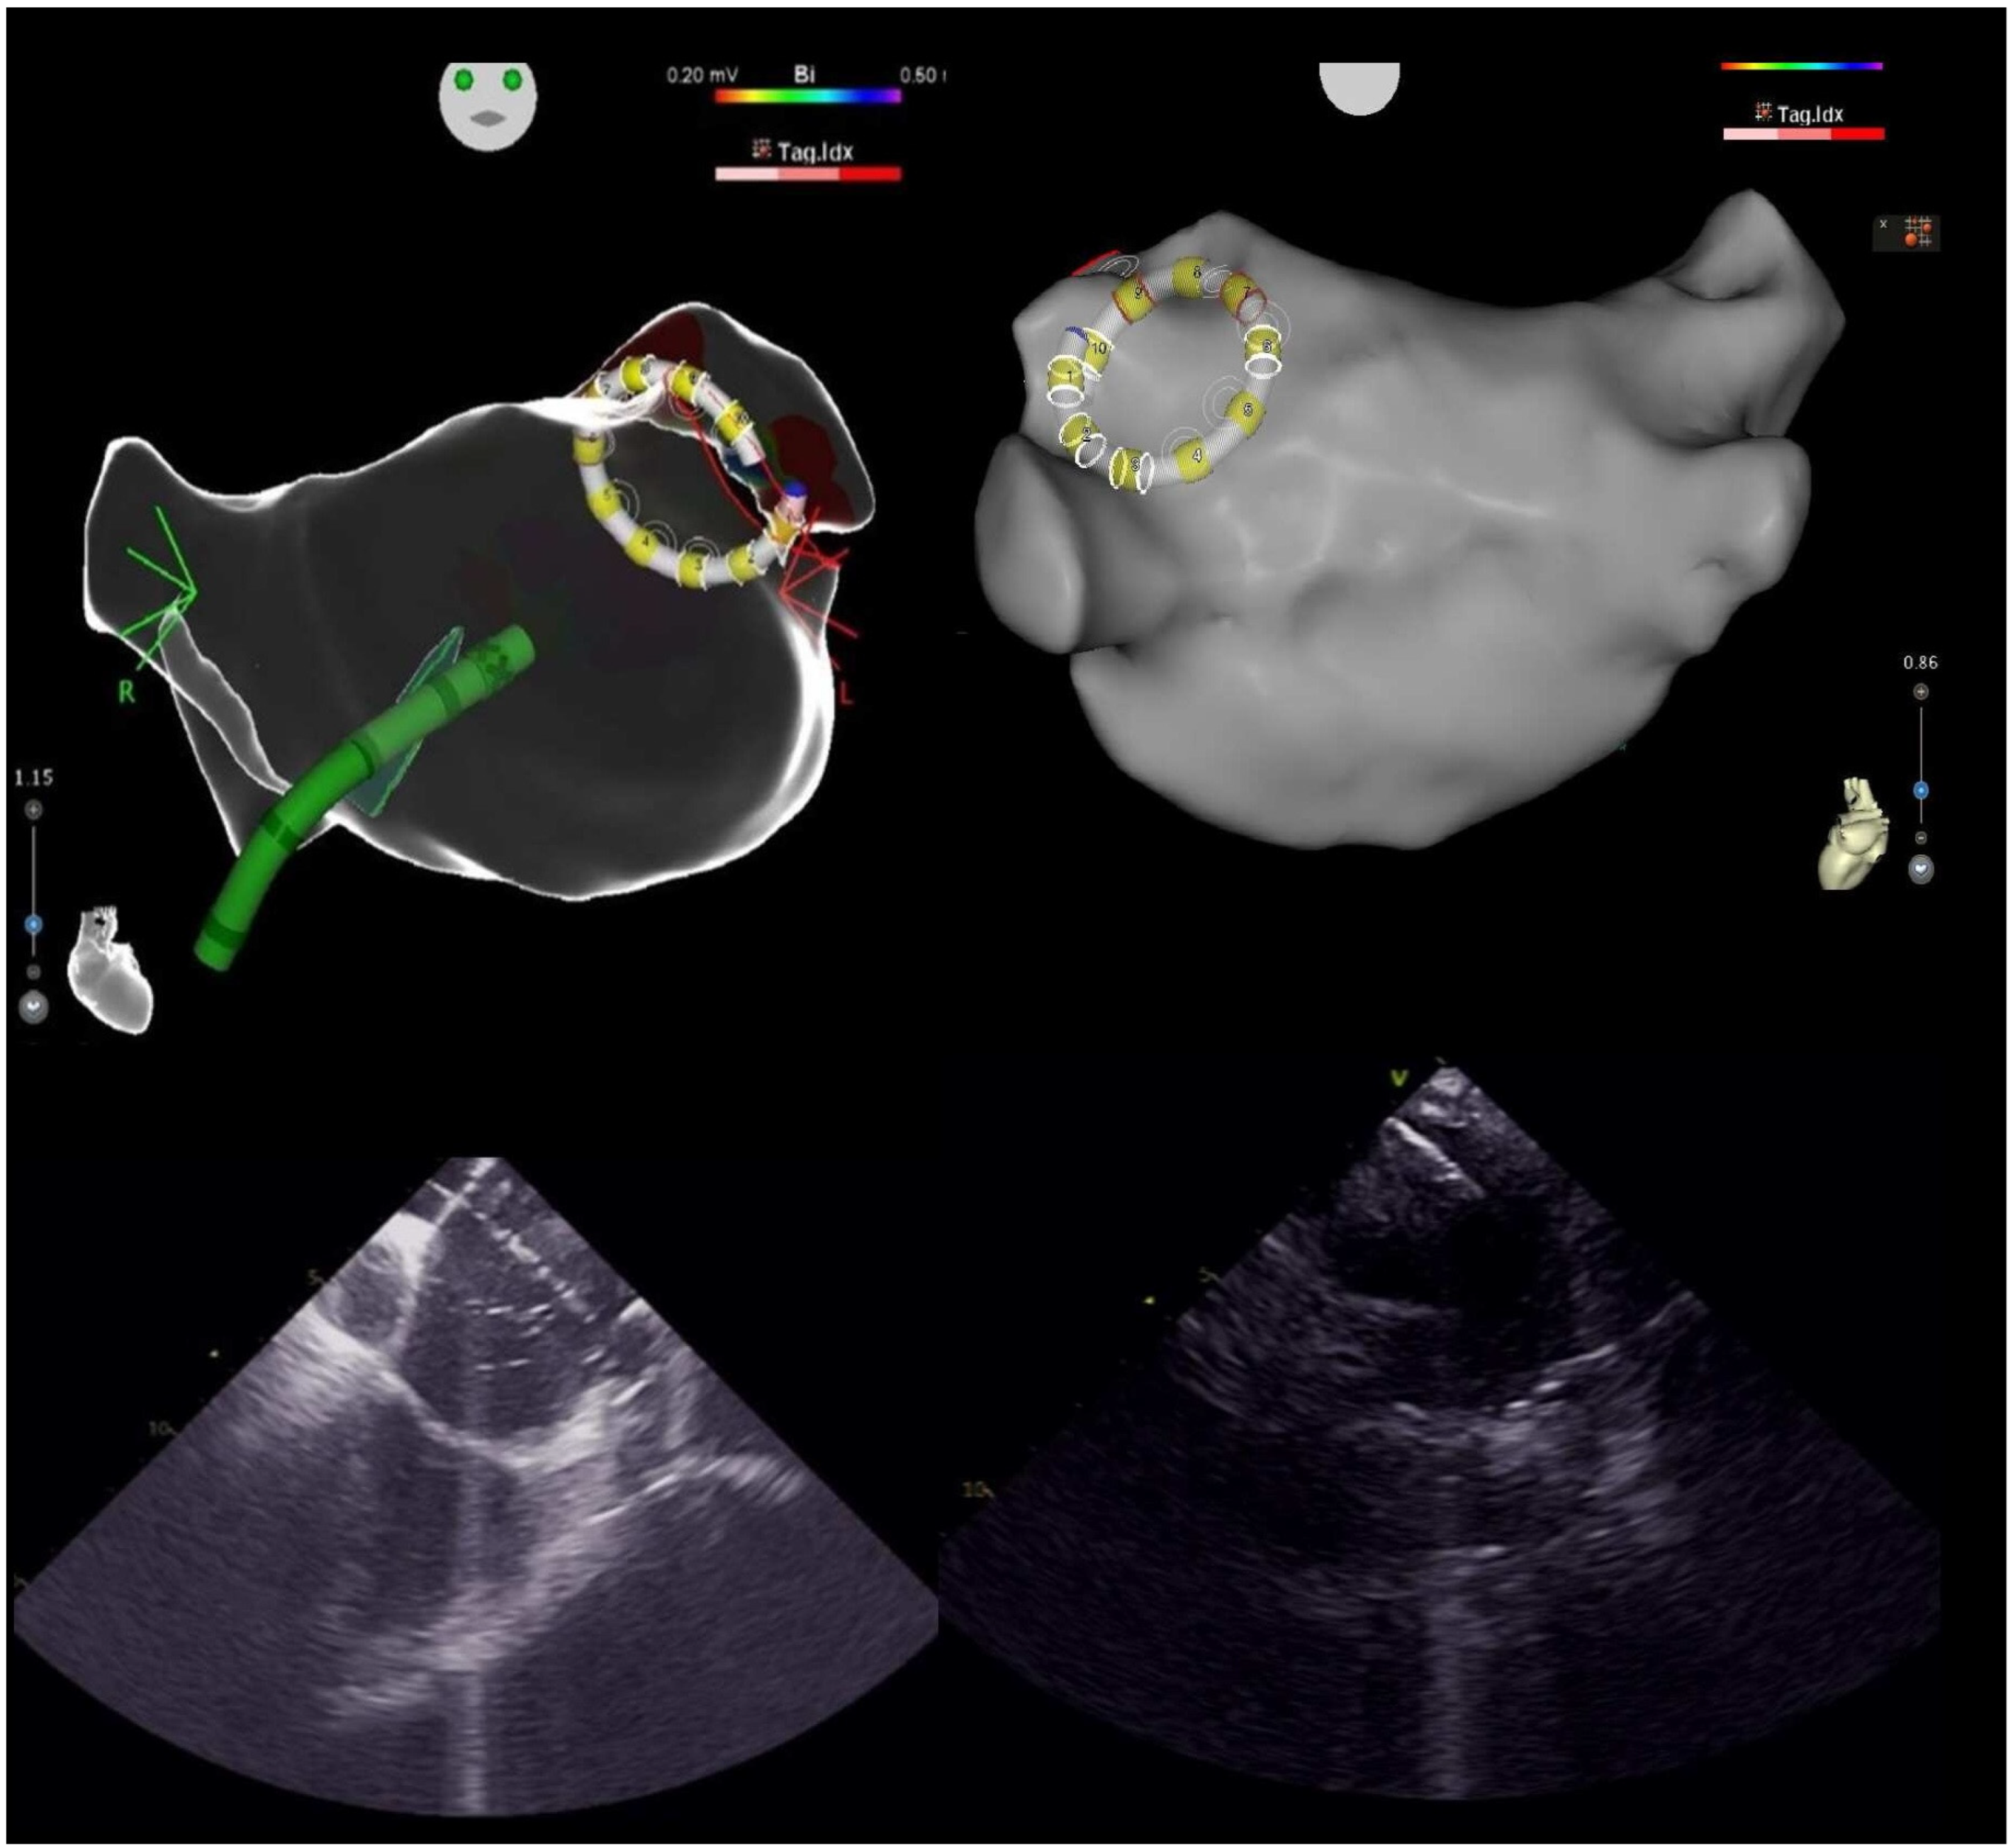

2.3. Intracardiac Echocardiography and CARTOSOUNDFAM MAP Module

2.4.1. Mapping Phase in ICE-Guided Cohort

2.4.2. Mapping Phase in Non-ICE-Guided Cohort

2.4.3. Ablation Phase